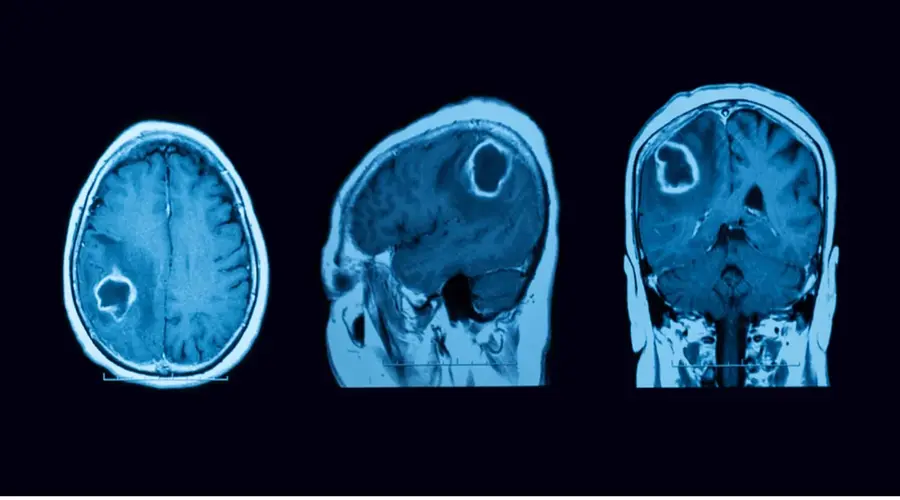

تصویربرداری و ارزیابیهای تکمیلی

- سیتی اسکن (CT Scan): در تشخیص اولیه آسیبهای مغزی ناشی از تومور مؤثر است، اما محدودیتهایی دارد. برخی تومورها مانند کیستهای آراکنوئید ممکن است در CT قابل مشاهده نباشند. همچنین افتراق برخی انواع تومور در این روش دشوار است. با این حال، در شرایط اورژانسی، پیش از آماده شدن نتایج MRI و MRS، جراحان میتوانند بر اساس یافتههای CT اقدامات فوری لازم را انجام دهند.

- امآرآی (MRI) مغز و کانال شنوایی داخلی: تصویربرداری دقیق از ساختارهای نرم ناحیه سی پی انگل و تشخیص نوع و موقعیت تومور.

- آنژیوگرافی تشدید مغناطیسی (MRA): برای بررسی انسداد یا تغییرات عروقی در محل تومور.

- تصویربرداری وریدی با تشدید مغناطیسی (MRV): بهمنظور ارزیابی جریان خون و انسداد در وریدهای مغزی.

- طیفنگاری تشدید مغناطیسی (MRS): برای تحلیل ترکیب شیمیایی بافت تومور و بررسی تغییرات متابولیک آن.